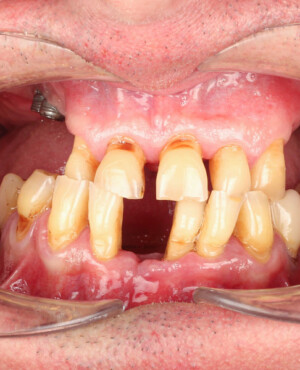

Protezarea pe implanturi dentare este soluția modernă, estetică și funcțională pentru înlocuirea dinților lipsă. Această procedură combină precizia chirurgicală cu tehnologia avansată de laborator pentru a reda pacienților zâmbetul natural, vorbirea clară și capacitatea de a mânca fără restricții.

După inserarea unui implant dentar – o rădăcină artificială din titan sau zirconiu –, urmează etapa de protezare, adică atașarea unei structuri protetice (coroană, punte sau proteză) care înlocuiește dintele lipsă.

- Consultația inițială și planificarea tratamentului (inclusiv tomografie CBCT)

- Inserarea implanturilor dentare (chirurgie ghidată digital)